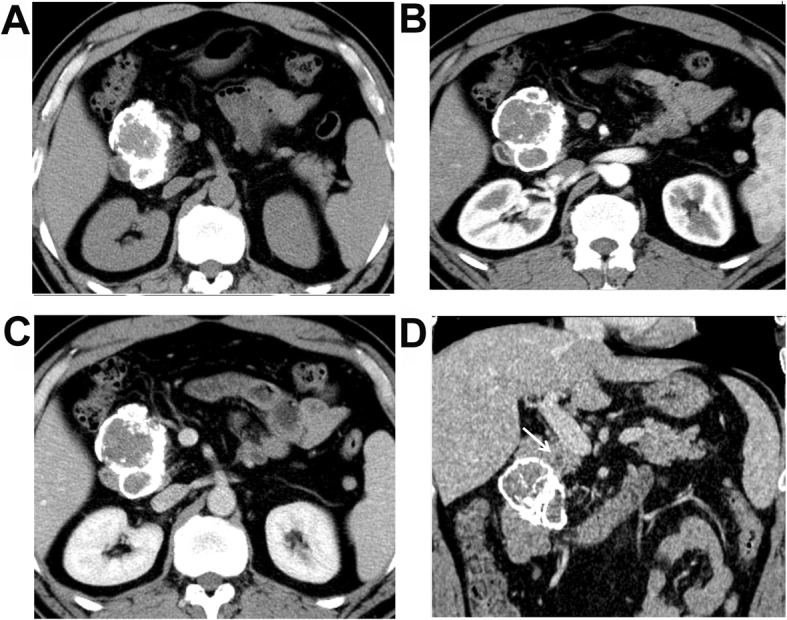

Fig. 2.

A 49-year-old male patient with discomfort in the upper abdomen. a Plain CT scanning + enhanced CT scanning showed pseudo-papillary neoplasm of pancreas (SPNP). a Plain scanning showed round solid changes at the pancreatic head, of which the boundaries were clear, and eggshell calcification was shown around the mass. b Low enhancement of the lesion in the arterial phase, which was lower than the normal pancreas. c Persistent enhancement of the lesion in the portal venous phase was shown. d Dilation of the pancreatic tube was shown on the reconstructed coronal image (white arrow)